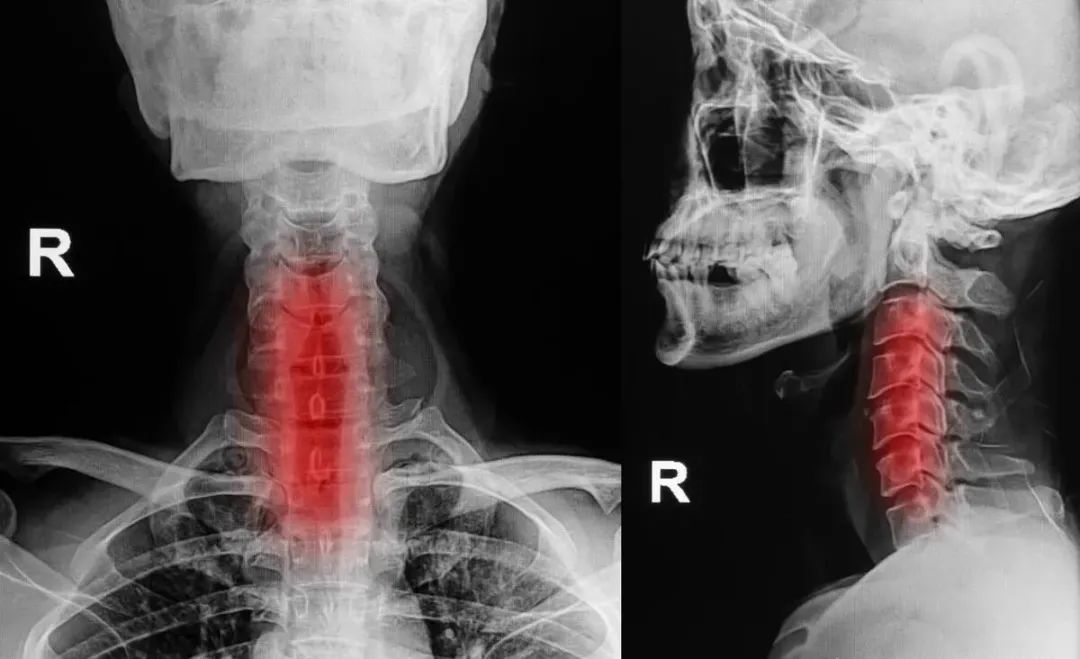

是指颈椎间盘退行性变,及其继发性椎间关节退行性变,所致脊髓、神经、血管损伤而表现的相应症状和体征。

由于椎间盘退变而使椎间隙狭窄关节囊、韧带松弛有柱活动时稳定性下降,进而引起椎体以及附近的关节和韧带等变性、增生、钙化,使颈段不稳定,形成恶性循环,最后发生脊髓、神经、血管受到刺激或压迫,引起一系列表现。